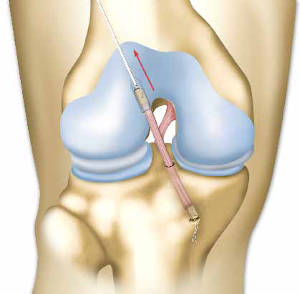

Ο χειρουργός πραγματοποιεί την επέμβαση κοιτώντας στο εσωτερικό του γόνατος μέσω μιας οθόνης. Η οθόνη αυτή συνδέεται με μία μικρή κάμερα (αρθροσκόπιο) που εισέρχεται στην άρθρωση μέσω μιας μικρής οπής (αρθροσκόπηση).

Ώστόσο, ο τένοντας που θα χρησιμοποιήσουμε, βρίσκεται κάτω από το δέρμα και για τη λήψη του απαιτούνται δυο μικρές οπές περίπου ενός εκατοστού, ή μία μόνο μεγαλύτερη οπή, οι οποίες όμως δε φτάνουν στο εσωτερικό της άρθρωσης. Αν ο χειρουργός επιλέξει να ανοίξει την άρθρωση (ανοιχτό χειρουργείο), το μέγεθος της τομής στο γόνατο ποικίλει (10 με 20 εκατοστά).

Δημιουργεί ένα τούνελ στο άνω άκρο της κνήμης και ένα δεύτερο στο μηριαίο οστό.Τα τούνελ αυτά χρησιμεύουν στο πέρασμα του νέου συνδεσμου στο οστό και στην καθήλωσή του. Η θέση αυτών των τούνελ υπολογίζεται έτσι ώστε οι οπές στην άρθρωση να αντιστοιχούν στα σημεία στήριξης του κανονικού συνδέσμου.

Ο χειρουργός με ειδική τεχνική, μέσω των μικρών οπών που έχουν ήδη ανοιχθεί, εισάγει τον νέο σύνδεσμο στο γόνατο. Η καθήλωση στα τούνελ γίνεται με διάφορες μεθόδους τις οποίες επιλέγει ο χειρουργός σας και με τη χρήση ειδικών υλικών μεταλλικών ή απορροφήσιμων [τα απορροφά δηλαδή ο οργανισμός μετά την ενσωμάτωση του τένοντα στο οστό (μετά από μερικές εβδομάδες)].